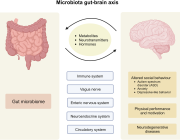

The human gut microbiome is a complex ecosystem that both affects and is affected by its host status. Zhavoronkov says this “microbiome aging clock” could be used as a baseline to test how fast or slow a person’s gut is aging

Previous analyses of gut microflora revealed associations between specific microbes and host health and disease status, genotype and diet.